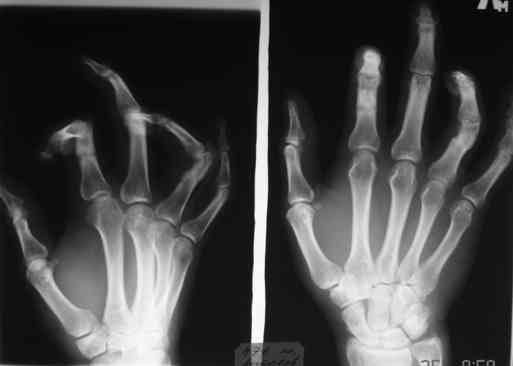

Комбинированная контрактура кисти

Уважаемые коллеги! Обратился больной с контрактурой 2-4 пальцев кисти. Травма год назад - рука попала в шнек. Планируется оперативное лечение.

Имеет-ли кто опыт укорачивающих остеотомий фаланг пальцев в подобных случаях?